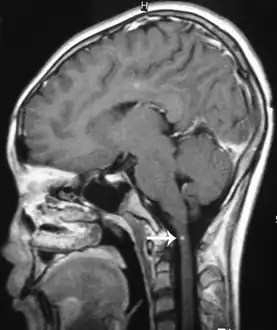

Brain image

Brain lesions, with invasion of brain matter, can be seen on a CT or MRI; however MRI findings may be inconclusive. Sometimes a hemorrhage, probably produced by migrating worms, is present and of diagnostic value.[3][12]